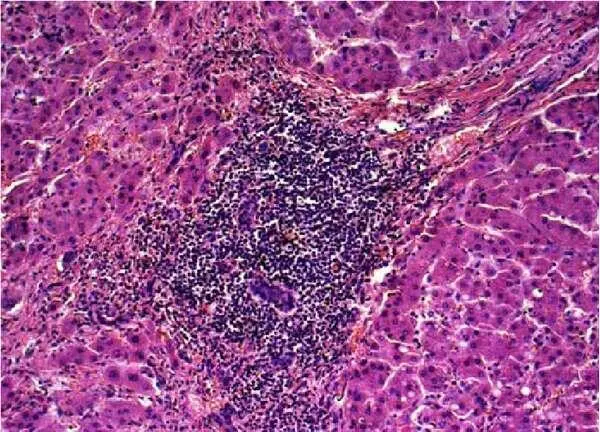

БП является наиболее точным методом в оценке активности воспаления и стадии фиброза при хронической НСV–инфекции. При анализе результатов БП больных НСV–инфекцией у 84,7% из них выявлен гепатит минимальной степени активности. Наиболее распространенным морфологическим признаком процесса была воспалительная инфильтрация портальных трактов (ВИПТ), представленная лимфоцитами и гистиоцитами (рис.22–23). ВИПТ отмечена в 100%, причем выраженная степень инфильтрации (3 и 4 балла по Кнодель) отмечена у 65 (51%) больных. Внутридольковые (лобулярные) некрозы (ЛН) выявлены у 56 (43,7%) больных, у 24 (18,8%) из них присутствовали ЛН выраженной степени (3 и 4 балла по Кнодель). Ступенчатые (перипортальные) некрозы (СН) отмечены у 55 (43%) больных, в том числе у 20 (15,6%) – резко выраженные.

Рисунок 22 – HCV умеренной степени активности: лимфоидная инфильтрация портального тракта с образованием фолликула; инфильтрат проникает в дольку; ступенчатые некрозы гепатоцитов; цепочки лимфоцитов в синусоидах. Окраска гематоксилином и эозином, Х100

Рисунок 23 – HCV умеренной степени активности: лимфоидная инфильтрация портального тракта с образованием фолликула; инфильтрат проникает в дольку; ступенчатые и внутридольковые некрозы гепатоцитов; деструкция и пролиферация желчных протоков; порто–портальная септа. Окраска гематоксилином и эозином, Х100.